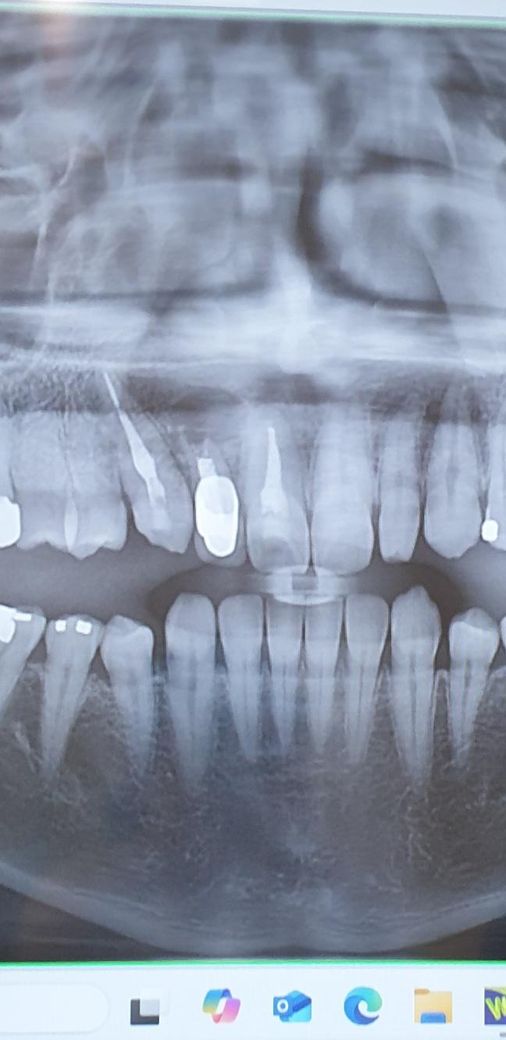

10년 전 치근단제거수술 후 재발했습니다..

송곳니?쪽인데 그당시 염증이 커서 옆치아들까지 신경치료했던 것 같아요

사진상에 보이는 치아상태라면 발치를 하셔야될것같습니다. 발치후에 임플란트 또는 브릿지 치료를 하셔야될것같습니다.

저정도면 이미 염증이 잇몸뼈 사방으로 퍼져서 치아와 관련된 치료가 무의미합니다 치근단 절제술이 불가능할정도로 치아 뿌리도 흡수가 많이된 상태입니다 빠른 발치를 추천합니다